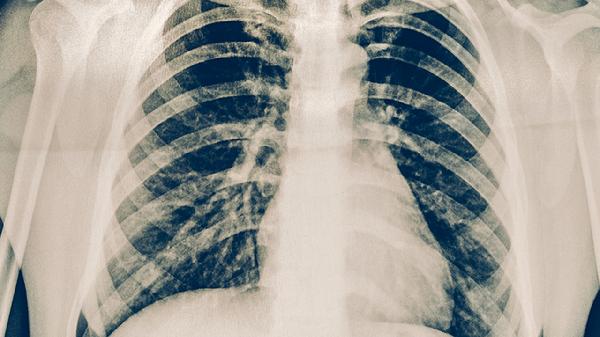

需复查胸部CT明确肺部病变范围,血常规判断感染程度,C反应蛋白评估炎症状态。若出现肺实变不吸收或胸腔积液,可能需支气管镜取材或穿刺引流。影像学进展可能提示特殊病原体感染。